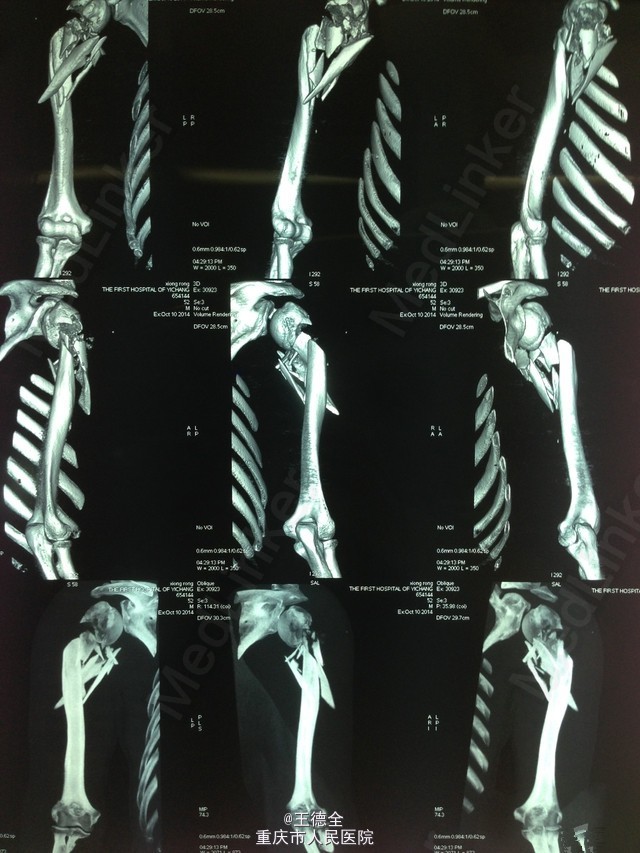

右肱骨近段粉碎性骨折

患者52岁,男性,以“右上臂外伤后疼痛出血伴活动受限4小时”入院。查体:右上臂肿胀明显,压痛,上臂中段可见一直径0.5cm伤口,上肢末梢血运和感觉可,手指活动可。入院后行清创术,抗炎、消肿治疗。8天后行切开复位植骨内固定术,术中输血600ml。